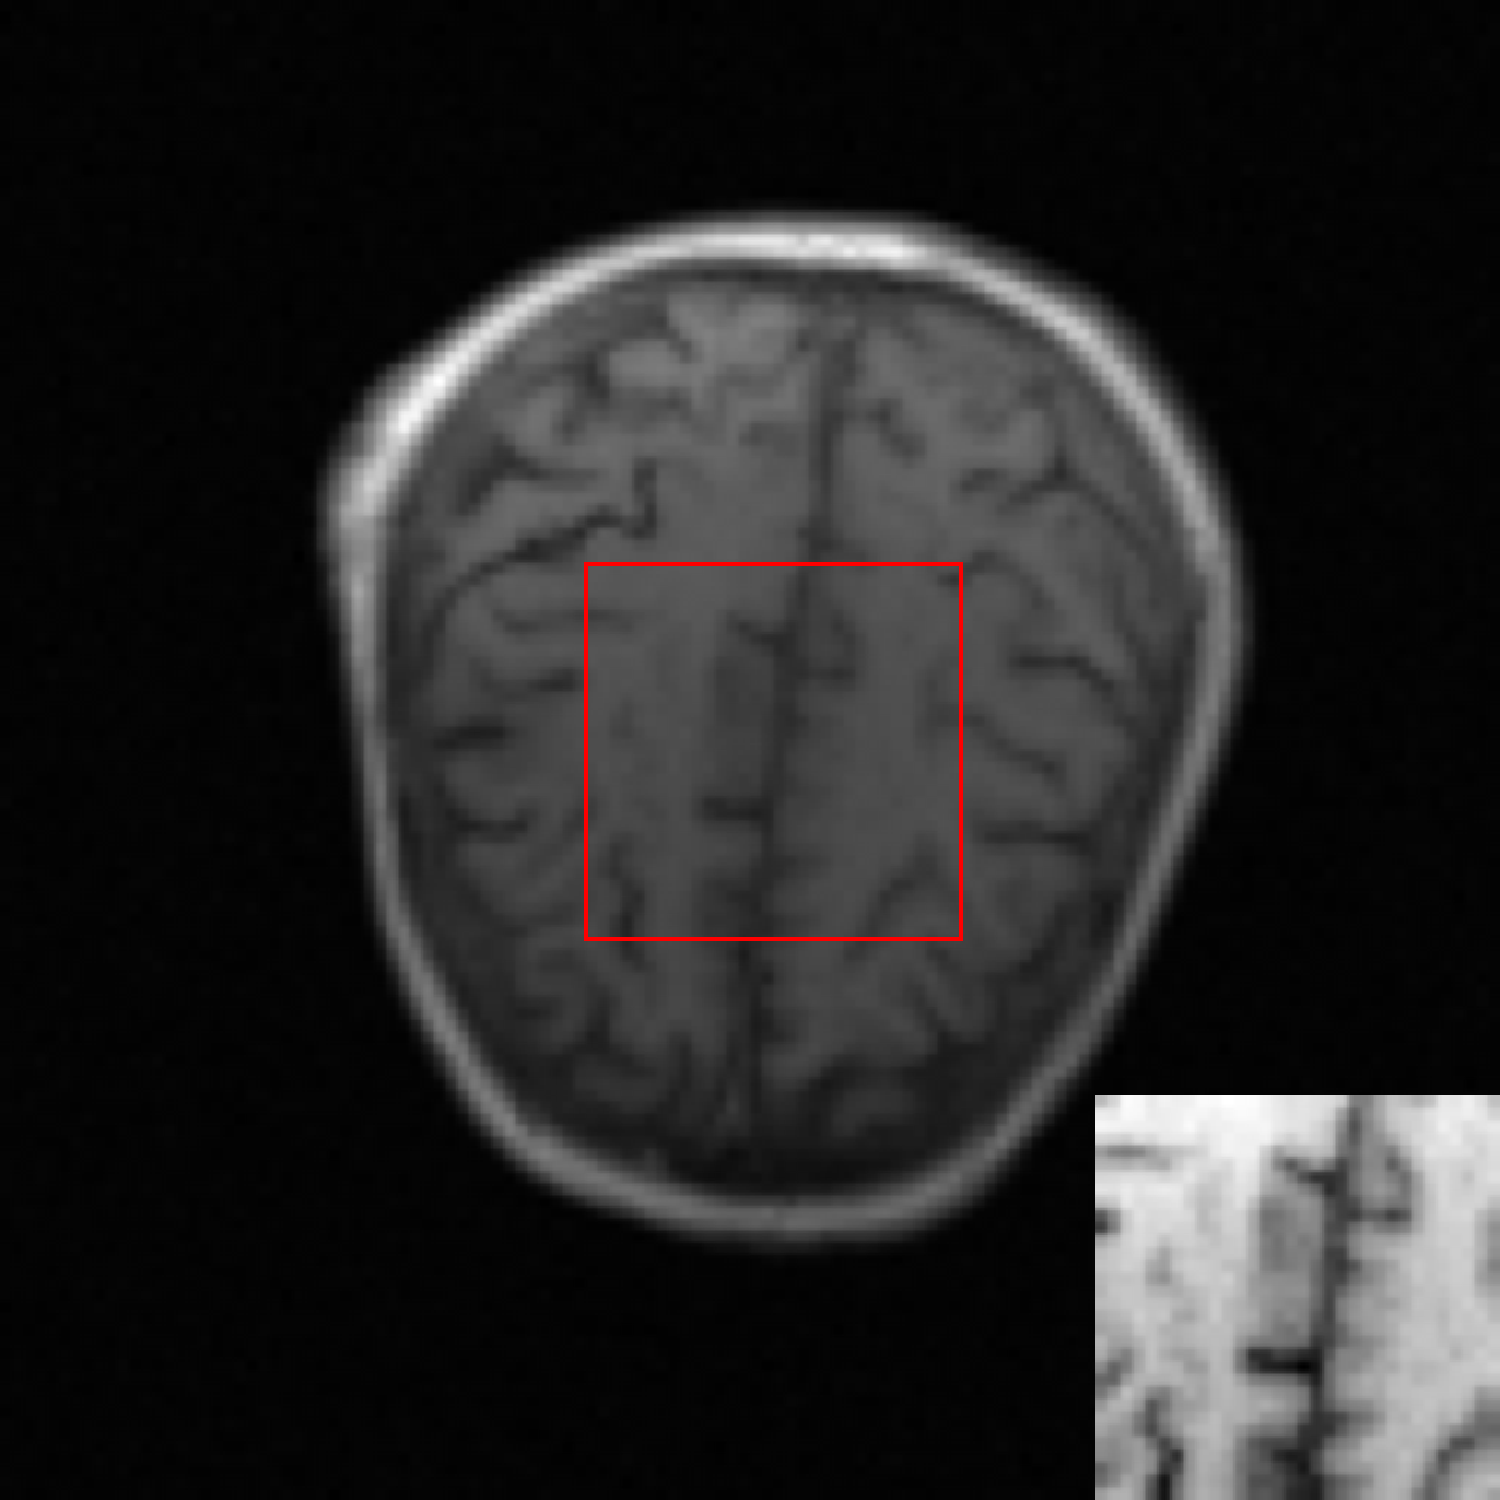

A simulation study was conducted. MR brain images in the NYU fastMRI Initiative database [11] (https://fastmri.med.nyu.edu/) were employed to form an ensemble of images that depict object properties sampled from the unknown SOM. Specifically, 3000 T1 weighted brain MR images corresponding to the magnetic field strength of 3T were selected, and these 3000 images were resized to the dimension of to be employed as real object images. Fully-sampled MR k-space data of these 3000 object images were simulated, and complex Gaussian noise were added to the k-space data. These 3000 noisy k-space measurement data formed the training dataset. An example of MR brain images, its corresponding k-space measurement data and the reconstructed image (i.e., IDFT of k-space measurement data) are shown in Fig. 2.